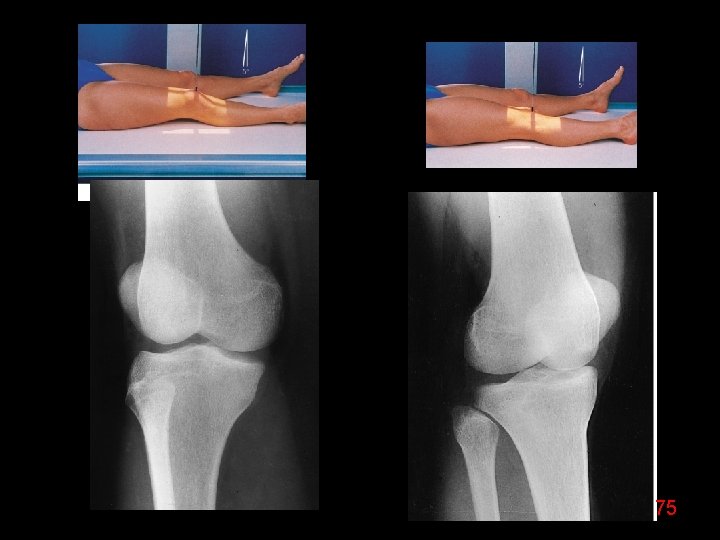

74

75